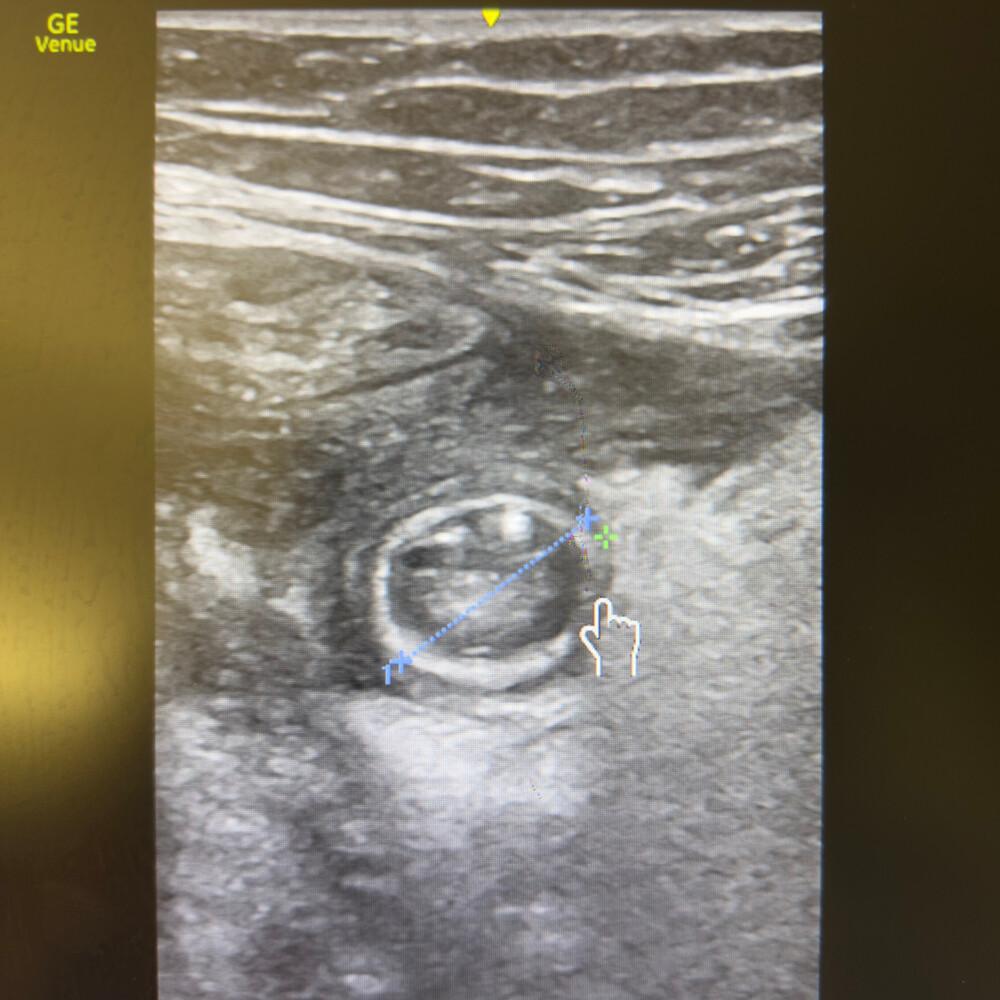

🔬 Aspect typique en coupe transversale

Image en cible (“target sign”)

Anneau hypoéchogène périphérique

Centre plus échogène

Absence de péristaltisme

- Appendice non compressible, en « cible », diamètre > 6 mm.